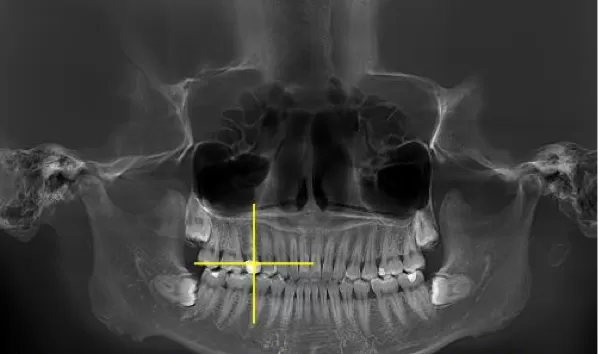

Rayons X avant le traitement

[Radiographie panoramique/Céphalogramme latéral]